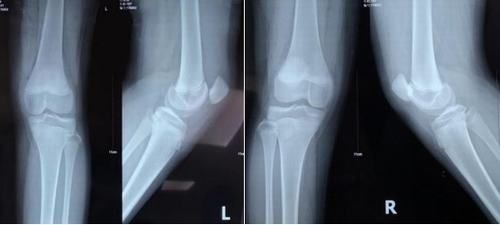

X線(xiàn)片示:髕骨脫位